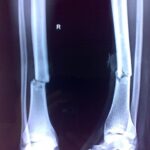

بخشی از نمونه کارها

نمونه کارهای قبل و بعد